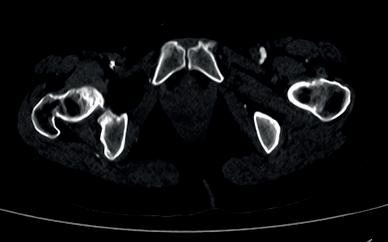

PeVD occurs when enlarged veins develop in the pelvis surrounding the uterus or ovaries, which can lead to severe chronic pelvic pain. Speaking to Interventional News, SIR Foundation chair and member of The VIVA Foundation board of directors Maureen P Kohi (The University of North Carolina, Chapel Hill, USA) referenced a call to action from the World Health Organization (WHO), which looked at global data citing pelvic pain as a central manifestation of the disease in women.

“The main treatment that we’ve been offering is OVE, and we know that the

data show a substantial improvement in chronic pain, but we’ve not been able to produce high-quality evidence to support that treatment option. Not only for the scientific community but also to our payers. Many women do not have insurance coverage for this procedure,” said Kohi. In women, these veins can be difficult to see and feel, Neil Mansho Khilnani (Weill Cornell Medicine, New York, USA)—a member of the EMBOLIZE steering committee—explained, which has driven “scepticism” over diagnosing and treating the pain. “The payers also hear this scepticism and jump on that as an opportunity to reduce expenses to their budget.”